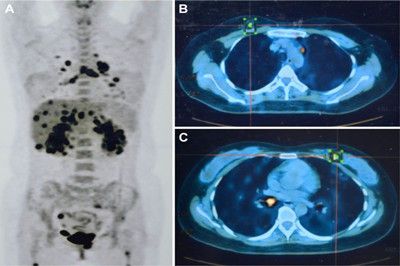

克唑替尼一线治疗ROS1重排肺癌老年患者的部分反应

引言 在肺癌患者中,精准医学背景下的个性化治疗已被证明比较有效。激活受体酪氨酸激酶ROS1重排是肺腺癌的一种分子亚型,可通过靶向治疗药物来抑制。克唑替尼(Crizotinib、Crizonix、赛可瑞、Xalkori)是一种被批准用于治疗间变性淋巴瘤激酶(ALK)阳性肺癌的小分子药物,在ROS1重排肺癌中也有活性。 在ROS1重排筛查方面,患者队列数据表明,ROS1阳性癌症患者年龄明显小于ROS1阴性患者。在最近的一份报告中,ROS1重排患者的中位发病年龄仅为49.8岁,明显低于ROS1阴性患者(62.3岁),甚至也低于ALK重排(51.6岁)。有研究者怀疑ROS1重排的分子筛查可以仅需限于较年轻患者。然而,老年患者对个性化治疗有很大的临床需求。老年患者特别需要能够快速改善生活质量的有效一线疗法,因为他们常患有常规疗法的禁忌症。 病例报告 一名90岁男性患者出现呼吸困难来我处就诊。病史:4个月前冠心病伴心肌梗死,双冠状动脉支架植入,无吸烟史。相关的合并症有心肌梗死后心包炎和慢性肾功能衰竭。 CT扫描显示肺左下叶肿瘤,最大为33mm,纵隔淋巴结受累。FDG-PET/CT扫描显示,原发病灶的SUVmax为19.7。此外,PET/CT在11L和5处发现肺门和纵隔淋巴结阳性。分期:IIIA期(cT2a,cN2,cM0)。支气管检查未发现纵隔淋巴结。 进行了核芯针穿刺活检。在组织学检查中,发现为实性为主的低分化腺癌。免疫组织化学细胞角蛋白7和甲状腺转录因子-1呈阳性,而p63和CD56免疫染色阴性,排除鳞状细胞和神经内分泌癌亚型。EGFR和KRAS突变以及ALK重排和MET扩增检测均为阴性。荧光原位杂交(FISH)分析显示ROS1重排阳性。因此,可以建立ROS1重排低分化肺腺癌的诊断。 鉴于肿瘤分期、合并症和患者年龄,患者不适合接受手术或常规化疗。讨论了原发病灶的立体定向放射治疗,但由于发现ROS1重排,肿瘤委员会讨论且患者知情同意后,患者接受克唑替尼治疗,剂量最初为250mg每日两次。第7天的实验室结果显示,先前偏高的γ-谷氨酰转肽酶(GGT)进一步增加,从正常上限(UNL)的两倍增加到四倍,谷草转氨酶(GOT)和天冬氨酸-氨基转移酶的升高(ASAT)从正常增加到UNL的两倍。同时,血清肌酐从1.6mg/dl增加到2.0mg/dl。 停药7天后,重新开始服用克唑替尼,减量至250 mg每日一次,而实验室检查参数改善,血清肌酐持续升高。患者在药物减量后第5天开始报告恶心、呕吐和腹泻。在克唑替尼药物减量后第15天,患者出现胸痛,停止用药。 停药3.5周后,患者以克唑替尼250 mg每日一次剂量重新开始治疗。使用H2阻断性药物治疗急性溃疡性纤维性化脓性食管炎后事件消退(4.5个月)。总之,在11个月的时间段内,不良事件导致停药11.5周。 开始克唑替尼治疗后2个月、3个月进行胸部X射线肿瘤评估。原发病灶大小分别从基线时26×50 mm减少到18×42mm、13×34 mm。4.5个月后的CT扫描显示,原发病灶部分反应:33 mm减至13 mm(CT),完全代谢反应(PET)。此时,CT和PET扫描显示,肺门和纵隔淋巴结仍然存在。第7个月和第10个月的胸部X光检查未见相关变化。11个月后,患者仍在接受治疗(克唑替尼每日一次250mg,推荐剂量的50%),对日常生活没有任何影响,并且ECOG体力状态评分为0分。 总之,本文报告了迄今为止年龄最大的ROS1阳性肺癌患者,表明ROS1重排不仅限于较年轻者、女性和癌症早期。 该病例说明,即使是存在合并症的老年患者,克唑替尼作为一线治疗也有效且安全性可控。 根据我们的发现,建议将老年晚期肺腺癌患者纳入ROS1重排的分子筛查范围。 本内容为医伴旅版权所有,转载请注明出处。 医伴旅:寻找优质医疗资源,伴您走上康复之旅